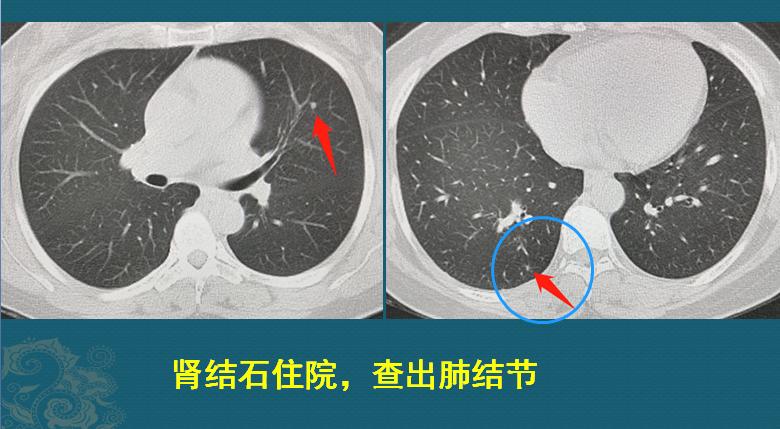

这是一位45岁女士,因为肾结石住院,胸部体检发现两个微结节灶,右肺的微结节还不到3mm:

这两个结节都属于低危结节,定期复查就好!<5mm的结节,首次复查可以选择6-12个月复查,不会耽误治疗。

因为疫情缘故,她在8个月的时候回来复查了CT,左边的没有变化,右边的长大了:

8个月的时间,从一个不足3mm的微结节,长成9mm的磨玻璃结节,速度非常快!以至于我们不敢确定就是肺癌。

我们把图像放大再看看细节,这个磨玻璃结节边界不清晰,内部有血管穿行,并略增粗,边缘有两处细线状胸膜牵拉,病人也没有咳嗽、发热症状,炎性指标都正常,这些辅助资料不太支持炎症:

最终做了胸腔镜下切除,病理是微浸润肺腺癌,基本治愈!因为<1cm的微浸润肺腺癌,手术治愈率几乎是100%的。